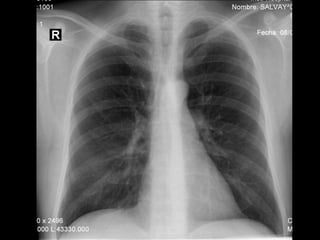

RADIOGRAFIA

• Radiografía normal

• Radiografía patológica

– Ensanchamiento mediastinal

• Técnica radiográfica

• Estructuras normales de tamaño o distribución atípica

• Estructuras vasculares

• Tumores